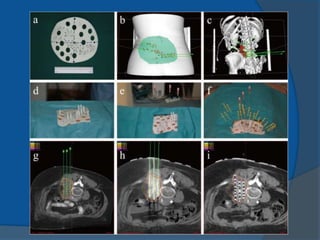

1980 Martinez and colleagues newbrachytherapy approaches to the treatment of prostate cancer were initiated temporary seeds inserted using a transperineal approach Dr Puthawala and colleagues pioneered a temporary seed technique of placing the needles, while visualizing them through an open laparotom Dr Whitmore and colleagues MSKCC began to insert I-125 seeds as a sole treatment through an open incision mid- 1980s transrectal ultrasound-guided, template-guided I-125 implantation procedure has become the primary technique of permanent seed implantation

1983 Hans HenrikHolm use of transrectal ultrasound to visualize the permanent placement of I-125 seeds via needles inserted through the perineum directly into the prostate implanting I-125 seeds into cancerous prostates, under the direction of axial imaging from a rectal probe mounted on a sledge-stepper (stepping unit). 1985 Blasko and Ragde the first transperineal, ultrasound- guided approach in the United States ultrasound-guided approach resulted in increased accuracy of needle and seed placement and relatively even distribution of seeds throughout the prostate it allowed computerized treatment planning of the implant rather than the use of simple nomograms ensuring the proper number, strength, and positioning of radioactive sources.